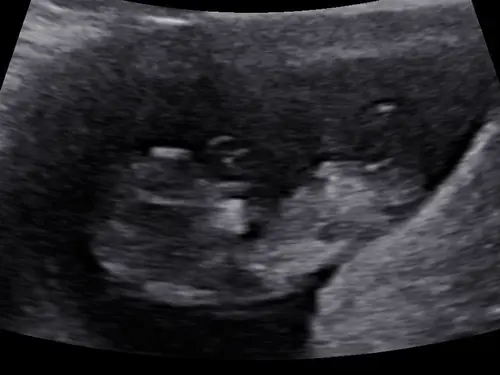

Hi, 12 weken nu. Heeft iemand een idee 😇🩷🩵